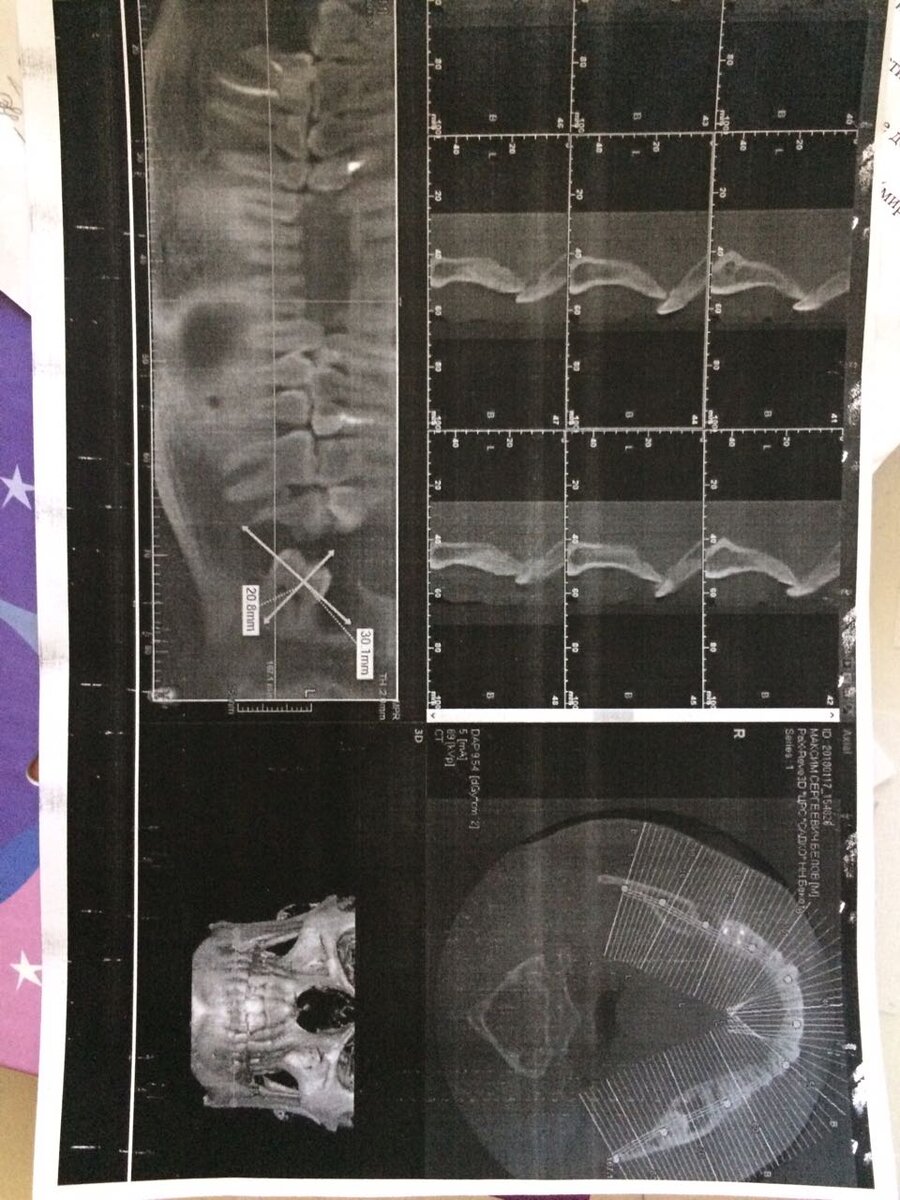

Многие как и я с возрастом чаще посещают стоматолога. И для этого есть множество причин. Но бывают случаи, которые требуют не просто лечения, а оперативного хирургического вмешательства. И на данном этапе важно, чтобы стоматолог Вас направил в челюстно-лицевую хирургию, а не пытался записать на очередной прием, затягивая проблему. Врач стоматолог Данилов М.В., работает в МЦ Веста-НН уже более 10 лет, он настоящий профессионал своего дела. Кисты часто встречаются в челюстных костях, поскольку эти кости содержат эпителий, оставшийся после развития зубов. А еще чаще они развиваются в области зуба мудрости, как у одного из наших пациентов. Киста - это патологическая полость, выстланная эпителием, содержащая жидкое или полужидкое содержимое. По мере роста кисты может наблюдаться заметная припухлость в щечной борозде, прилегающей к причинному зубу. Эту припухлость часто описывают как имеющую "яичную скорлупу. Это означает, что при надавливании на нее может возникнуть ощущение растрескивани